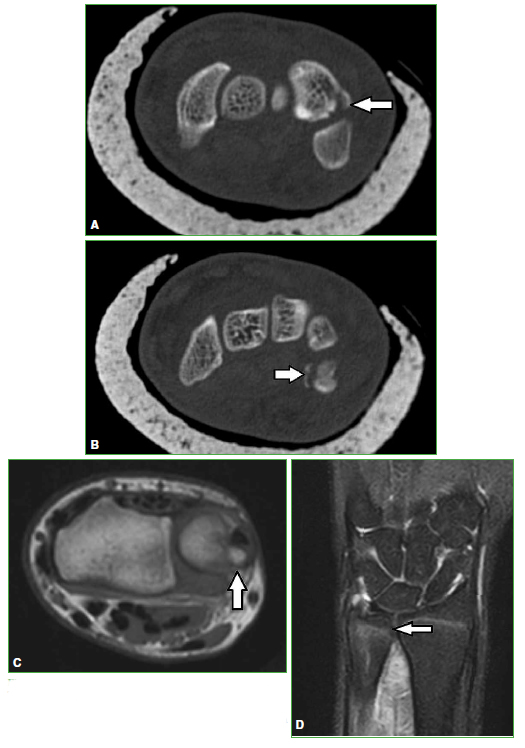

Figura 6.

Fracturas de huesos de la muñeca en dos deportistas. Tomografía computarizada, cortes axiales. Se observa fractura de los huesos pisiforme (A) y piramidal (B) (flechas) de un atleta. Resonancia magnética, cortes axial T1 y coronal STIR. Se visualiza una fractura del cúbito (C y D) (flechas) en otro atleta.